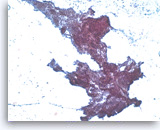

Metastatic adenocarcinoma of the colon,

Pancreas FNA, Cell Block.

The tumor cells are positive for CDX-2 (nuclear staining). This finding along with keratin 20 immunopositivity and the cytomorphologic features supports a colorectal primary.

10X

Metastatic adenocarcinoma of the colon,

Pancreas FNA, Cell Block.

The tumor cells are positive for CDX-2 (nuclear staining). This finding along with keratin 20 immunopositivity and the cytomorphologic features supports a colorectal primary.

10X